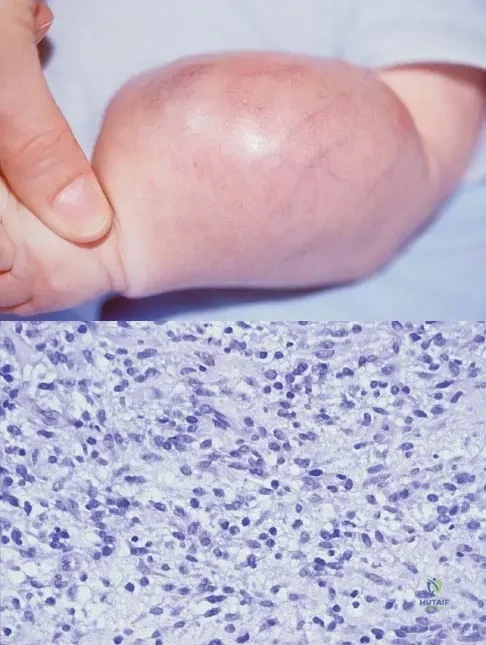

Question 40

An infant is born with a mass that involves both the volar and dorsal compartments of the left arm. A clinical photograph and biopsy specimen are shown in Figures 41a and 41b. What is the best initial course of action?

Explanation